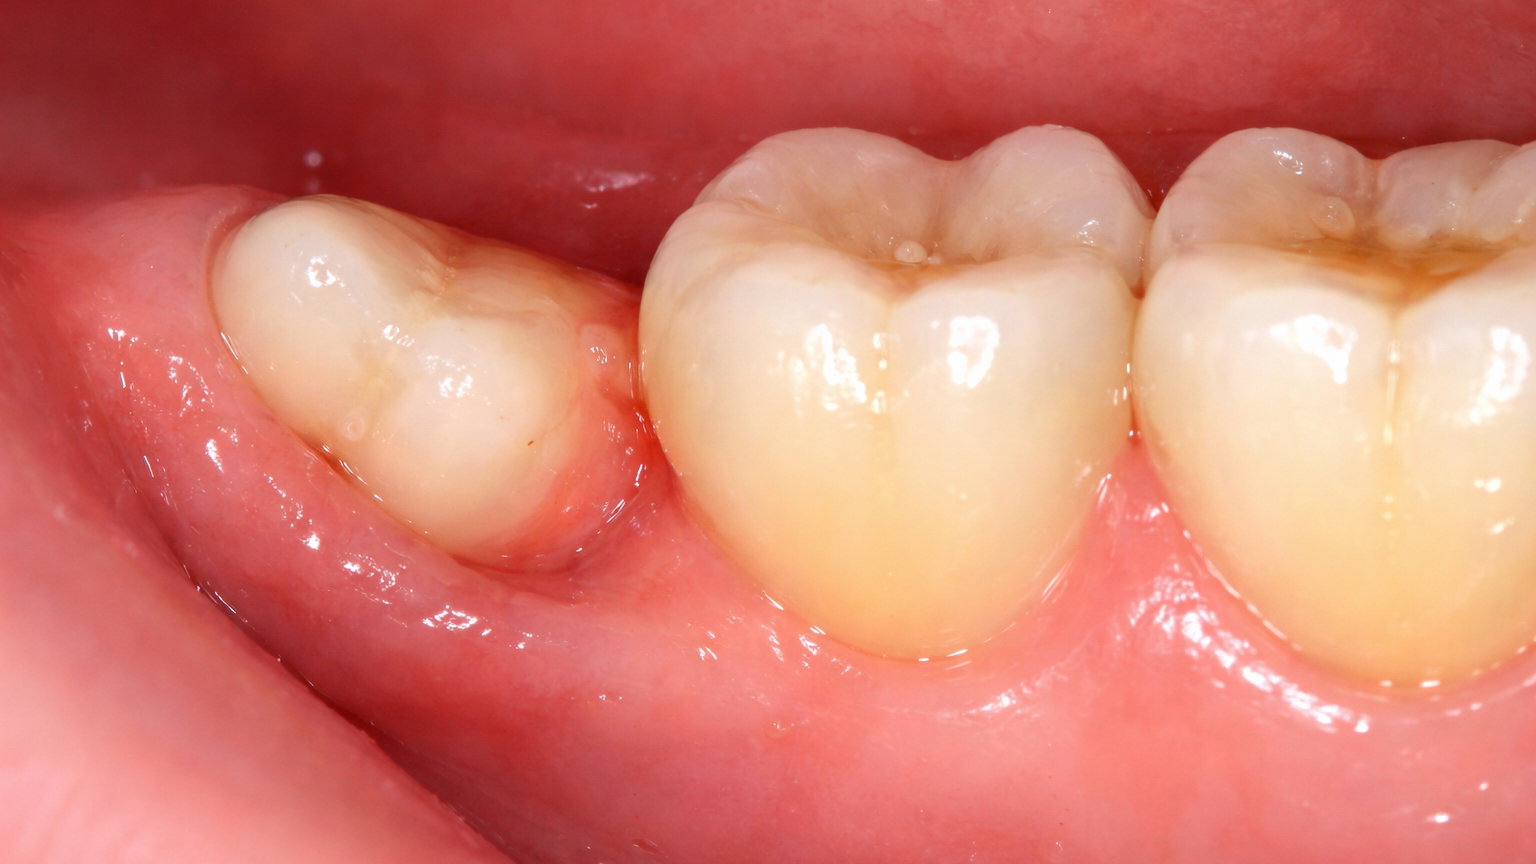

Image showing an impacted wisdom tooth pressed up against the second molar, with mild gum inflammation

Not every person will require the removal of their wisdom teeth. If there is adequate space in the jaw and the teeth erupt fully, in proper alignment, and can be kept clean, they may remain in place without issue. However, a significant number of people experience impaction, where one or more wisdom teeth become trapped beneath the gum line or against adjacent teeth due to lack of space. Impacted teeth can grow at an angle, remain partially erupted, or become completely lodged within the jawbone. This condition can lead to a variety of problems, including localized pain, swelling, and infection of the surrounding gum tissue. Partially erupted teeth create an opening that is difficult to clean, allowing bacteria to accumulate and potentially cause pericoronitis, a painful gum infection. There is also a risk of cyst formation around the impacted tooth, which can damage bone and neighbouring tooth roots. Furthermore, wisdom teeth, even when fully erupted, are situated in a hard-to-reach area of the mouth, making them susceptible to decay and increasing the risk of cavities on the adjacent second molars.